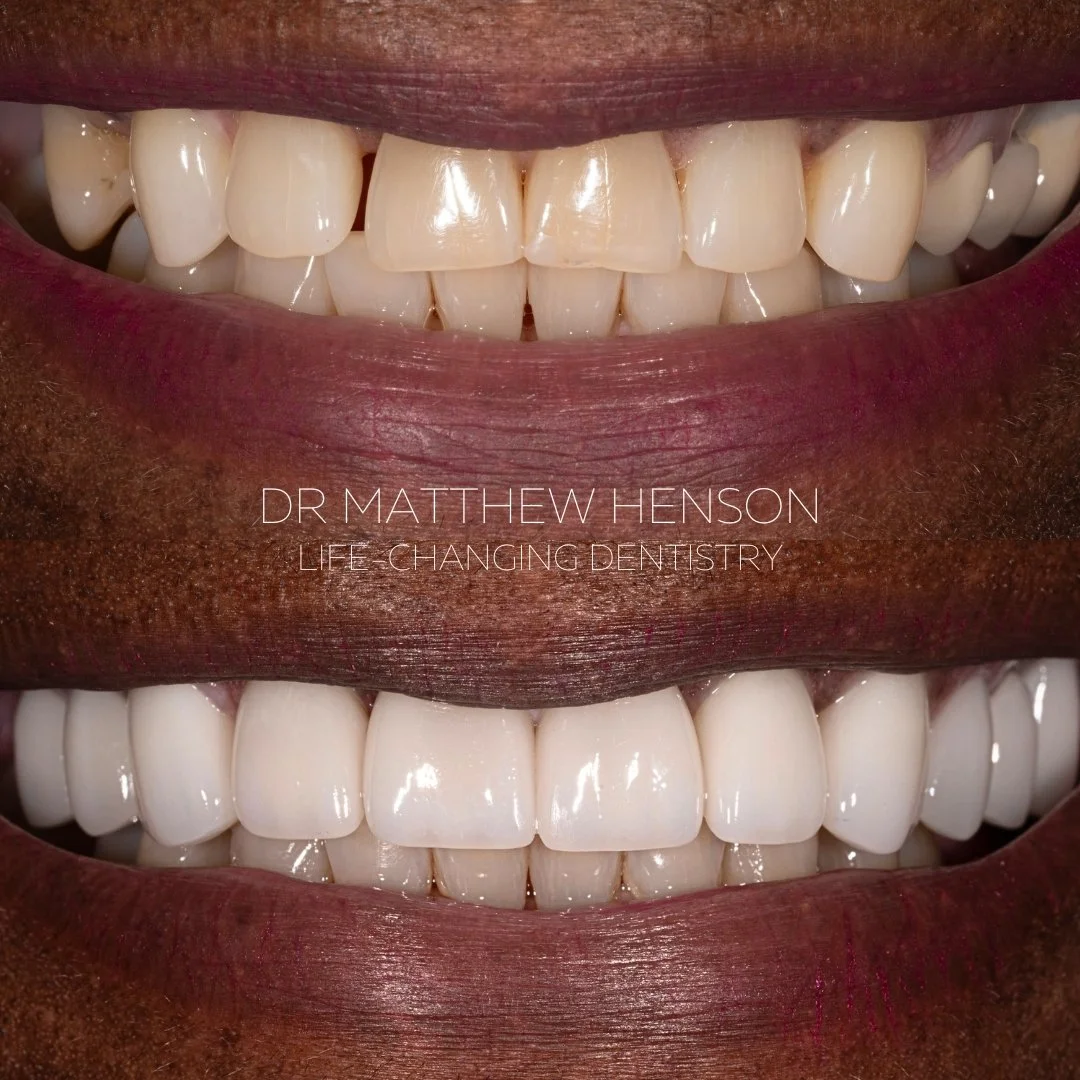

Patient A.N.

Two bridges and 5 veneers to give a more youthful appearance

Patient sent photo of herself from high school saying she wanted her old smile back

Two bridges and 5 veneers to give a more youthful appearance

Patient sent photo of herself from high school saying she wanted her old smile back